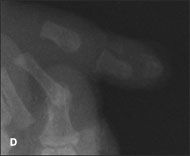

Complete duplication of the left thumb in a baby boy was noted at birth; a radiograph of the thumb showed 2 proximal and distal phalanges with 1 first metacarpal bone (A and B). He also had fusion and incomplete bony duplication of the right thumb; a radiograph of this digit showed normal proximal and distal phalanges plus a small tiny bony remnant of the proximal and distal phalanges of an accessory thumb (C and D).

The infant had no other apparent abnormalities. He had been born at term after a normal pregnancy and uncomplicated delivery. The mother had 2 sisters; each had 1 child with ulnar polydactyly-nubbin accessory digits on the little fingers.